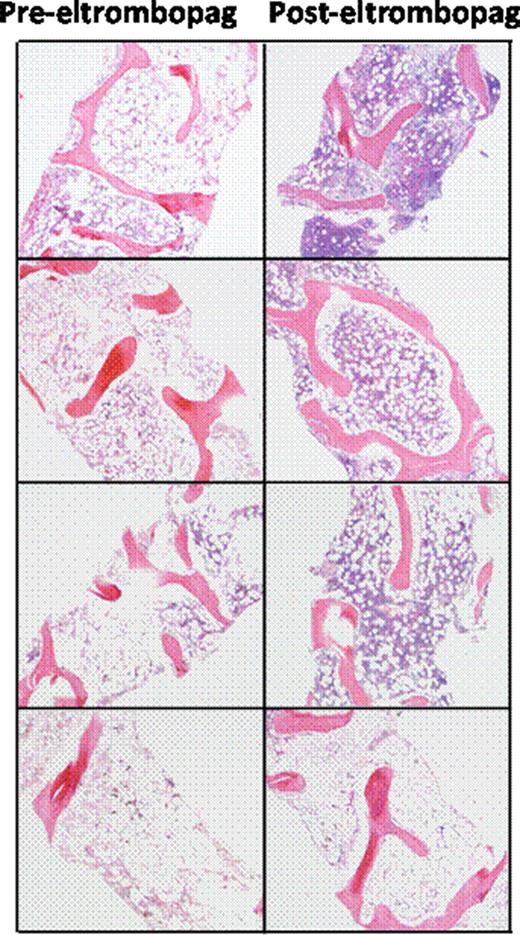

Severe aplastic anemia (SAA) is characterized by trilineage marrow hypoplasia and a paucity of hematopoietic stem cell (HSC) progenitors. SAA is treated with immunosuppressive therapy (IST) or allogeneic HSC transplantation (HSCT), with a successful outcome after either treatment in a majority of patients. However, 20–40% of patients without a suitable donor for HSCT and a suboptimal response to IST may have persistent severe thrombocytopenia. Thrombopoietin (TPO) is the principal regulator of platelet production, and it exerts its effects through binding the megakaryocyte progenitor TPO receptor mpl, which stimulates production of mature megakaryocytes and platelets. Several lines of evidence support the concept that signaling through mpl also influences expansion and maintenance of primitive HSCs and multi-potent progenitor cells. Eltrombopag, is a small molecule TPO receptor agonist that stimulates mpl, and increases platelet counts in patients with chronic immune thrombocytopenic purpura (ITP). It is approved for the treatment of chronic ITP (Promacta®). We conducted a non-randomized, pilot phase II study of eltrombopag in SAA patients who remained severely thrombocytopenic at least six months after one or more rounds of IST (clinical trials.gov identifier NCT00922883). Consecutive patients fulfilling the inclusion criteria received eltrombopag 50mg daily with dose escalation every two weeks to a maximum dose of 150mg daily. Primary end points assessed after three months of treatment were changes in peripheral blood counts (platelets, hemoglobin, absolute neutrophil counts), with hematologic response criteria defined a priori for each lineage. Secondary endpoints included the incidence of bleeding events, and health related quality of life. Patients who achieved hematologic responses were maintained on eltrombopag through an extended access protocol. We completed our planned accrual of twenty five patients, and 22 are evaluable for response to date. Median age was 45 years old (range 18–77 years), and the median time from the last course of IST was 13 months (range 6–54 months). Median follow up time was 9 months (range 1–24 months). Nine of twenty two patients (41%) achieved hematologic responses: seven of twenty-two patients (32%) achieved platelet responses with transfusion independence for eight weeks or greater; six patients had improved hemoglobin levels after starting treatment (mean hemoglobin increase of 3.8 g/dL) and 4 patients who were previously dependent on red blood cell transfusions have achieved transfusion-independence. Five neutropenic patients had increased neutrophil counts after treatment with eltrombopag (mean increase 660 cells/uL). Plasma TPO levels did not predict for hematologic response to eltrombopag. Serial bone marrow biopsies performed on patients with hematologic responses demonstrated normalization of trilineage hematopoiesis and cellularity in three of four responders receiving a year or more of therapy, with no increase in reticulin fibrosis (Figure 1). These results represent the first evidence that TPO stimulation can expand the HSC pool in humans, with clinically meaningful trilineage hematologic improvements in patients with SAA, resulting in transfusion-independence and improved quality of life with a simple daily oral regimen. Updated response data on the full 25 patients will be presented at the Society's meeting.